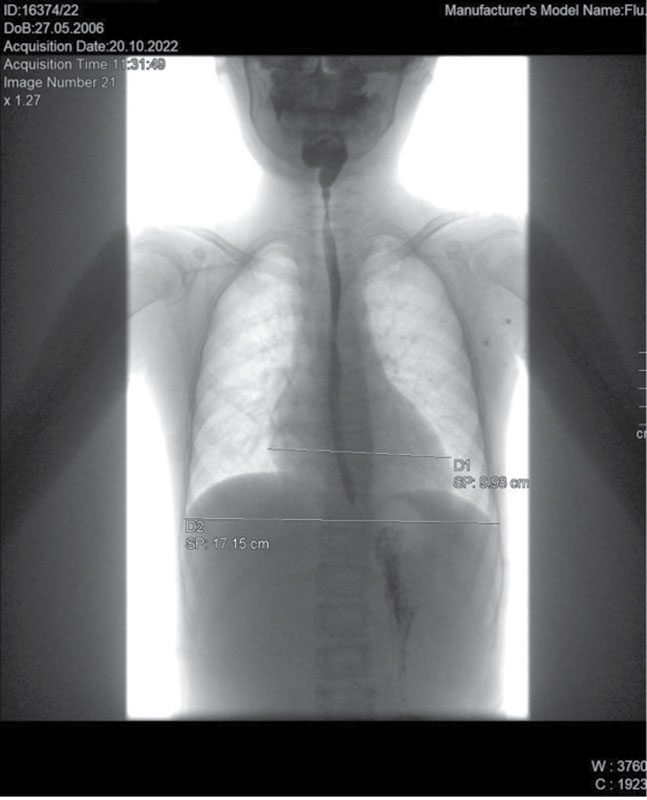

Рис. 2. Рентгенологическое исследование органов грудной клетки. Сердечно-грудной индекс – 0,57 (горизонтальный размер тени сердца – 9,72 см)

Рентген органов грудной клетки: отмечается повышенный горизонтальный размер тени сердца, однако в динамике отмечается снижение до 9,72 см. Сердечно-грудной индекс также снизился до 0,57 (рис. 2).

По результатам повторной консультации кардиолога было сделано заключение о сохраняющемся ремоделировании сердца по дилатационному типу с положительной динамикой на фоне проводимого лечения в виде уменьшения выраженности дилатации и улучшения сократительной способности ЛЖ. При пересчете измерений межжелудочковой перегородки (МЖП) и задней стенки ЛЖ данных за гипертрофию миокарда недостаточно, z-score МЖП – 1,4, задняя стенка ЛЖ до 1,9. Оценить ФК не представляется возможным ввиду ограничения физической активности. Диагноз: «Кардиомиопатия, дилатационный фенотип. Нарушение ритма сердца: хроническая суправентрикулярная тахикардия. ХСН стадии 2А».